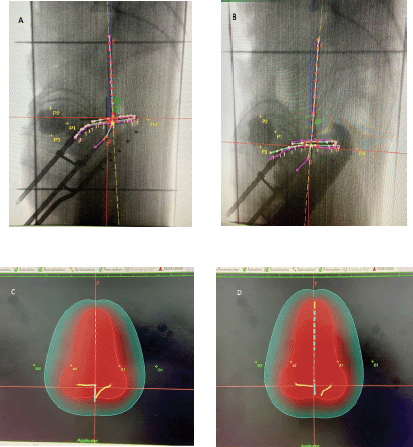

Patients differed between the two comparison groups. The individual anatomical variations among patients may be a possible confounding factor. However, when two methods, i.e., the combination of RR+VP and RR alone, were applied to the same patient during different insertions, patients could act as their own internal control, thus eliminating this possible confounding effect. In an attempt to account for this, subset analysis of ICB fractions was performed on five such women who received at least one fraction with each method. In these women, the ICB sessions that were done using the same tandem length, angle and ring size during both the combination procedure (RR+VP) and the conventional procedure (RR alone) were compared. This subset analysis was performed as an intrapatient comparison, and the results are presented in Table 3. For the same dose prescribed to point A in both groups, the mean dose to the ICRU rectal point was 40.5% of the prescription dose in the RR+VP group and 55.5% in the RR group. There was a 15.0% reduction in the mean dose to the ICRU rectal point (p = 0.013). The mean dose to the ICRU bladder point was 59.9% of the prescription dose in the RR+VP group and 46.5% in the RR group. There was a 13.4% increase in the mean dose to the ICRU bladder point (p = 0.019). The mean point B doses, mean reference volumes (Vref) for the BT part of treatment, mean 60 Gy reference volumes (V60Gy) and mean total TRAK values were similar in both groups. Figure 1 shows simulation and planning images of the fractions received by the same patient with the two methods of rectum separation.

Figure 1. Planning images of one patient who completed 50 Gy EBRT, followed by three fractions of 7 Gy HDR BT using the same tandem ring applicator with a tandem length of 6 cm, angle of 45° and a ring size of 3 cm during two consecutive fractions. (A) Applicator placement during the first fraction performed using a RR alone for rectal separation. P1 = ICRU bladder point, P4 = ICRU rectal point. (B) The same applicator placement during the second fraction using a combination of rectal retractor and radio-opaque vaginal packing (RR + VP). P1 = ICRU bladder point, P4 = ICRU rectal point. (C) During the first fraction delivered with RR alone, a pear-shaped reference volume (Vref) enclosed within a 7 Gy (100%) red isodose curve was 149.10 cc (dh × dw × dt) and that a 60 Gy reference volume (V60Gy) represented by a 2.4 Gy (33.6% of 7 Gy) green isodose curve in this case was 643.1 cc (H × W × T) (see text details on measuring the dimensions and calculating the 60 Gy volume). The point B dose was 1.6 Gy (22.7% of point A dose), ICRU rectal point dose was 4.17 Gy (59.6% of point A), ICRU bladder point dose was 2.5 Gy (35.3% of point A) and TRAK value was 0.00392 Gy. (D) During the second fraction delivered using the same applicator parameters but a combination of RR + VP for rectal separation, the reference volume (Vref) enclosed within a 7 Gy (100%) red isodose curve was 156.6 cc (dh × dw × dt), and the 60 Gy reference volume (V60Gy) enclosed by a 2.4 Gy green isodose curve was 682.4 cc (H × W × T). The point B dose was 1.6 Gy (23.8% of point A dose), the ICRU rectal point dose was 2.7 Gy (38.2% of point A), the ICRU bladder point dose was 3.7 Gy (52.9% of point A) and the TRAK value was 0.00406 Gy. In this patient, the BT fraction delivering the same prescribed dose to point A and treating equal 60 Gy isodose volumes, using a rectal retractor in combination with radio-opaque vaginal packing (RR+VP) reduced the dose to the ICRU rectal point by 1.5 Gy (21.4%) compared to the fraction delivered using a RR alone.